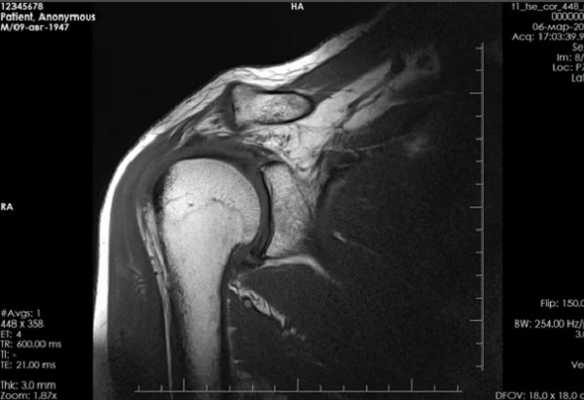

Фото компьютерной томографии плечевого сустава

Плечевой сустав самый подвижный в организме человека. Огромный диапазон перемещений приводит к его нестабильности, поэтому вывихи и травмы регистрируются часто. Дислокация суставной головки из своего ложа увеличивает вероятность повреждения, что часто приводит к дегенеративному процессу, при котором окружающие сустав ткани постепенно разрушаются и перестают нормально функционировать. Что можно обнаружить на томограммах? КТ плечевой кости демонстрирует сложность перелома, смещение отломков и угол, образуемый их положением. Способность визуализировать изображения в осевой, сагиттальной и корональной плоскостях, а также в трехмерном формате, помогает в интерпретации картины повреждения и предоперационном планировании.

Наиболее часто КТ плечевого сустава выполняют по поводу травматических повреждений. Они различаются по механизму альтерации: падение на вытянутую руку, прямой удар и пр. Врач-рентгенолог после анализа томограмм выявляет причину, а ортопед определяет оптимальную тактику ведения. Иногда повреждение может быть настолько серьезным, что пациенту необходимо эндопротезирование плечевого сустава.

Рентгенограмма и компьютерная томограмма у пациента с тяжелым переломом и вывихом правого плечевого сустава до операции